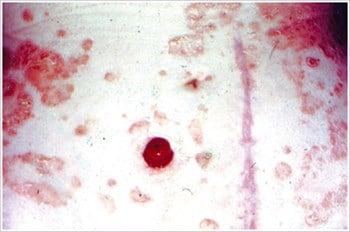

Pyoderma Gangrenosum3

Description/causes : Une maladie inflammatoire de la peau souvent observée chez les patients atteints d’une maladie inflammatoire de l’intestin (MII) telle que la maladie de Crohn ou la colite ulcéreuse.

Symptômes : Ulcères irréguliers, rouges, douloureux, infectés, avec des marges roulées rouges à violettes ; apparaissent sur les jambes, les fesses, le visage et la région péristomiale.